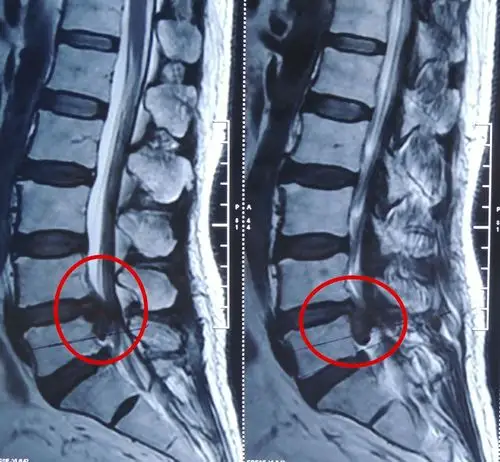

椎间孔镜治疗腰椎间盘突出症,腰椎管狭窄症经典病例分享

一例"简式"技术椎间孔镜下腰椎间盘突出髓核摘除核磁影像 - 好大夫

腰及右腿坐骨神经痛3年,加重2个月,经右外侧椎间孔镜手术取出突出髓核